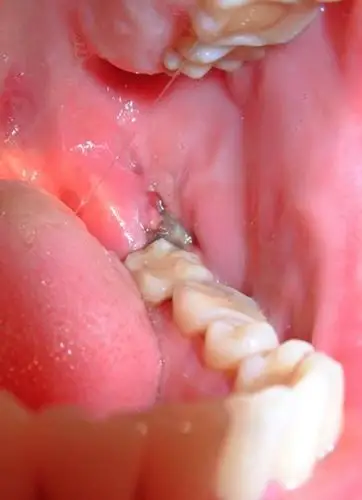

牙龈增生

【求助】牙龈增生图片,治疗,请大家支招